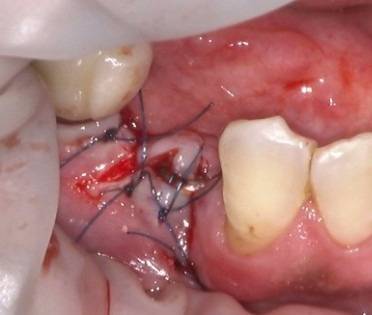

インプラント埋入手術+GBR(骨造成術)

術中

インプラント埋入手術では、局所麻酔・歯肉の切開・インプラント床の形成・埋入・縫合などを行いますがこれは一連の流れであり、途中でやめることはあまりありません。